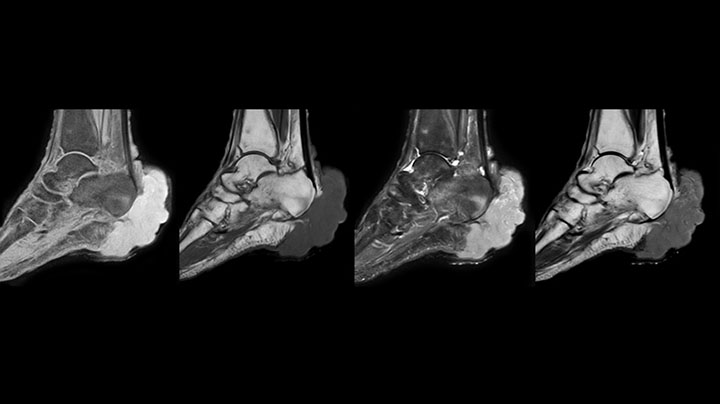

MRI examination on Prodiva 1.5T of a 72-year-old female with a malignant melanoma in the ankle. mDIXON TSE provides excellent fat suppression, without the distortion that is often seen at such extremities.

Prodiva imaging of the hand covers the fingertips and includes the full wrist as well. The dS MSK M coil is easy to use.

Scan time 2:55 min, FOV 160 mm, acq voxels 0.55 x 0.83 x 3.0 mm.

Scan time 4:19 min, FOV 160 mm, acq voxels 0.55 x 0.80 x 3.0 mm.

Scan time 2:50 min, FOV 160 mm, acq voxels 0.70 x 0.99 x 3.0 mm.